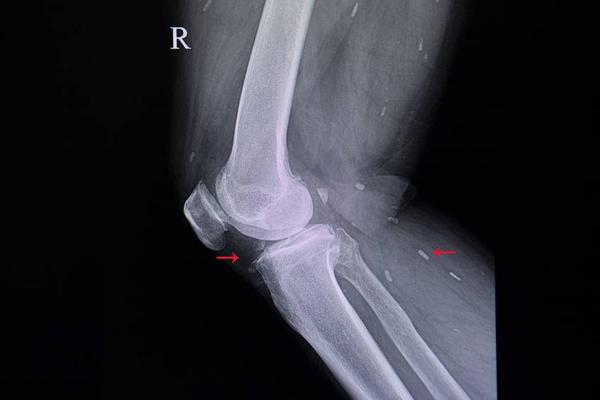

1、关节炎

关节炎在生活中可谓是较为常见,其主要原因是因关节出现退行性病变,而除关节本身的退行性病变外,也可能是其他疾病引起的炎症,但因不同原因说引发的关节炎会有不同的症状表现,因此患者一定要学会区分。

例如,因退行性病变引起关节炎,其主要表现为关节功能障碍,并伴有骨骼老化。但若是因其他疾病引发的关节炎,一般则会有不同程度的全身症状。